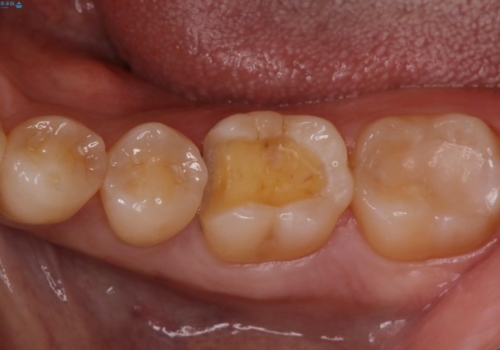

- 下の奥歯が黒いことが気になり来院された患者様です。

レントゲンなどから隣接面にも、う蝕があることが判明しました。

一部歯に保険治療で使用されている材料が劣化していたため、う蝕と一緒に取り除いて劣化の少ないセラミックに置き換わりました。